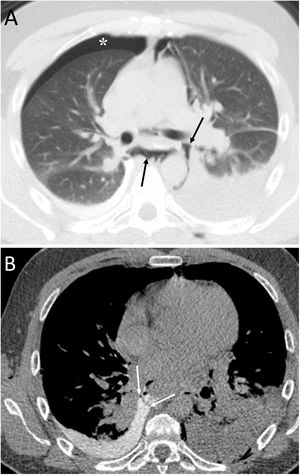

Spontaneous PM is not due to an apparent cause such as chest trauma. Rarely, it can be associated with pneumorrhachis, which is the presence of air in the spinal canal4 (Fig. 1). It is due to the passage of air from the submandibular and retropharyngeal spaces to the epidural space through the neural foramina.1 In general, this condition is benign and self-limited.1

A 63-year-old woman with dyspnoea. A) The chest X-ray (lateral projection) showed pneumomediastinum with air delimiting the anterior wall of the intrathoracic trachea and the cardiac silhouette (white arrows). B) The computed tomography also revealed the presence of air in the medullary canal (black arrows). Subsequent radiological studies showed resolution of the extrapulmonary thoracic air (not shown).